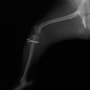

■ 症例20 ポメラニアン 8ヶ月 1.8kg

左右膝蓋骨脱臼 グレードⅢ

2ヶ月前から間欠的跛行が認められ、両膝の膝蓋骨脱臼整復術を行った。

手技は縫工筋及び内側広筋の解放、脛骨粗面の外側転位、滑車ブロック形造溝術、内外側関節包の縫縮を選択し実施した。

右側の膝蓋骨脱臼は上記手技で整復されたものの、左側はそれのみでは膝蓋骨が浮く様子が認められた。その為、PDS縫合糸にて膝蓋靱帯を1糸のみ縫合し、靱帯の縫縮を行った。